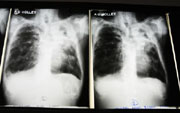

| X-rays from a tuberculosis patient |

Smoking does not cause tuberculosis; bacteria cause the infection. But the study says smoking affects the nervous system in a way that makes an inactive case of TB more likely to develop into an active one.